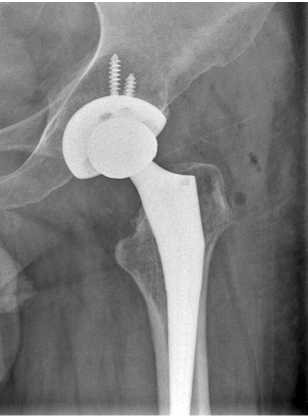

07.03.23 произведена операция в объеме резекции головки бедренной кости, установки артикулирующего спейсера из костного цемента с клиндамицином (4,5 г) (рис. 5). Выбор клиндомицина обусловлен близким к линкомицину механизмом действия и антимикробным спектром (в анамнестических данных пациента есть указания на положительный эффект применения линкомицина), а также высокой элюционной способностью препарата [25]. Микробиологическое исследование тканей, взятых интраоперационно, возбудителя не выявило.

Рис. 5. Рентгенограмма правого тазобедренного сустава пациента К. в первые сутки после операции установки артикулирующего цементного спейсера с двухслойной головкой. Наружная цементная мантия содержит 4 г клиндамицина